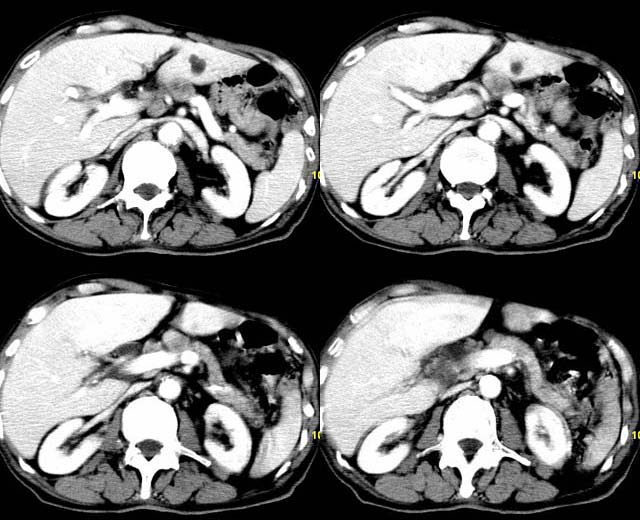

以下是引用余辉在2007-12-6 22:23:00的发言:[br]胆囊内多枚结石影,胆管全程扩张,右肝内病灶强化符合脓肿表现现(左肝病灶图像未传完),考虑急性梗阻性化脓性胆囊胆管炎合并肝多发脓肿(建议补传左肝病灶图像)